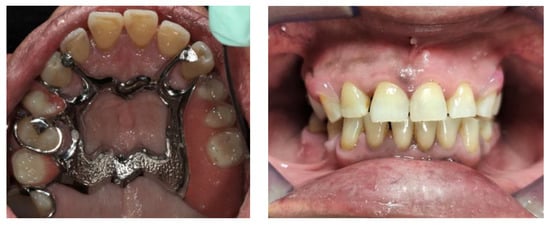

2. Case Report

The subject involved in this clinical study was a healthy woman, 54 years old. The request of this patient was to improve her mouth both functionally and aesthetically, which was altered because of the partial edentulism (Kennedy Class II). She asked to avoid any invasive surgery. During the anamnesis, she declared not to be affected by any systemic pathology (e.g., diabetes, hypercholesterolemia or hypertension). She also declared not to be affected by an allergy to any medication or similar drugs; she declared not to be subjected to any pharmacologic treatment except some analgesic therapy to treat sporadic headaches. The patient claimed to smoke 20 cigarettes a day for more than 20 years. The next step was to perform an objective examination, associated with a series of intraoral pictures (Figure 1, Figure 2, Figure 3, Figure 4 and Figure 5) and to the analysis of a radiographic exam (orthopantomography, Figure 6) that was acquired 10 months earlier when the same subject underwent the therapy and the teeth extraction 4.7–4.8. The objective examination showed poor oral hygiene, with plaque accumulation as well as the presence of many pigmentations due to excessive smoking. The radiography showed bilateral bone atrophy together with periodontal damage for most of the residual dental elements. These conditions represented a limitation to the insertion of implants for a fixed prosthesis.

During the fifth appointment, both the prostheses were delivered without having to do any retouching (Figure 19 and Figure 20), and the following clinical evaluations were performed:

Figure 1. Frontal view.

Figure 4. Upper view.

Prosthesis 03 00038 g004

Figure 5. Lower view.

Figure 19. Finished and polished prosthesis realized with the analog procedure.

Figure 20. Finished and polished prosthesis realized with the hybrid procedure.